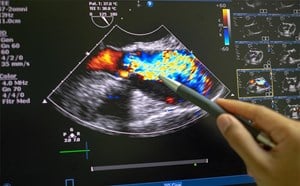

A point-of-care ultrasound was performed to further evaluate his dyspnea. The cardiac ultrasound showed moderately depressed left ventricular ejection fraction, left atrial enlargement, mitral annulus calcification, grade 2 diastolic dysfunction and apical and inferoseptal hypokinesis. The lung ultrasound showed diffuse B-lines.

Recent studies have shown that ARDS patients with left ventricular diastolic function has a significant increase in extravascular lung water detected by lung ultrasound, however, it is only a qualitative not a quantitative measure.3 Conventionally, the most accurate way of measuring the LV filling pressure which correlates with the mean PCWP is through an invasive procedure using the pulmonary artery catheter, but modern practice and clinical trials have shown that it is rarely used in critically ill patients.4 By contrast, real time echocardiography can be used as an alternative method. Specifically, diastology can be used as a quantitative assessment of left ventricular preload to differentiate cardiogenic from noncardiogenic pulmonary edema. In general, LV preload is determined by LV relaxation and compliance. LA pressure is a dynamic variable and can be changed by preload that affects the transmitral pressure gradient rather than intrinsic diastolic function which can provide useful information in settings when the visualization of the IVC is limited.

To measure diastolic dysfunction, start by obtaining an apical four chamber, place pulse-wave doppler over the tips of the mitral valve leaflets, and transmitral velocity times can be measured (Image 2). Peak E wave velocity correlates with early diastolic filling rate, mitral annular e’ velocity reflects LV relaxation rate (Image 3), and both values are used to calculate E/e’ which correlates with left ventricular filling pressures.